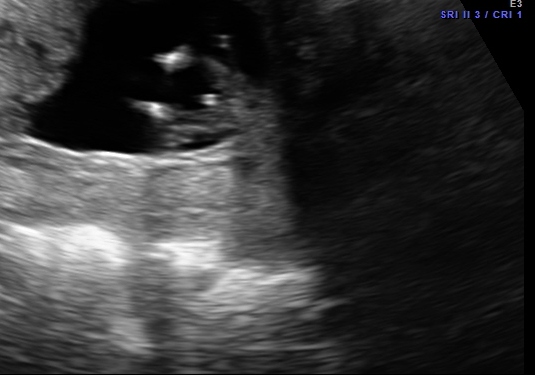

Hi - I am not even sure if there is a nub in the pictures below taken at 12 weeks 1 day. Any guesses would be appreciated!! Tech guessed boy based on potty shot.

Picture 1 looks like a boy nub. Picture 2 looks like girl nub! I'm not sure potty shots are supposed to be very accurate this early. I think the skull looks girly in all of them but really it could go either way!

PIc 1 looks boy. Other's looks girl to me...even potty. Skull looks boy. 50/50 for me! I suck at this though :)))